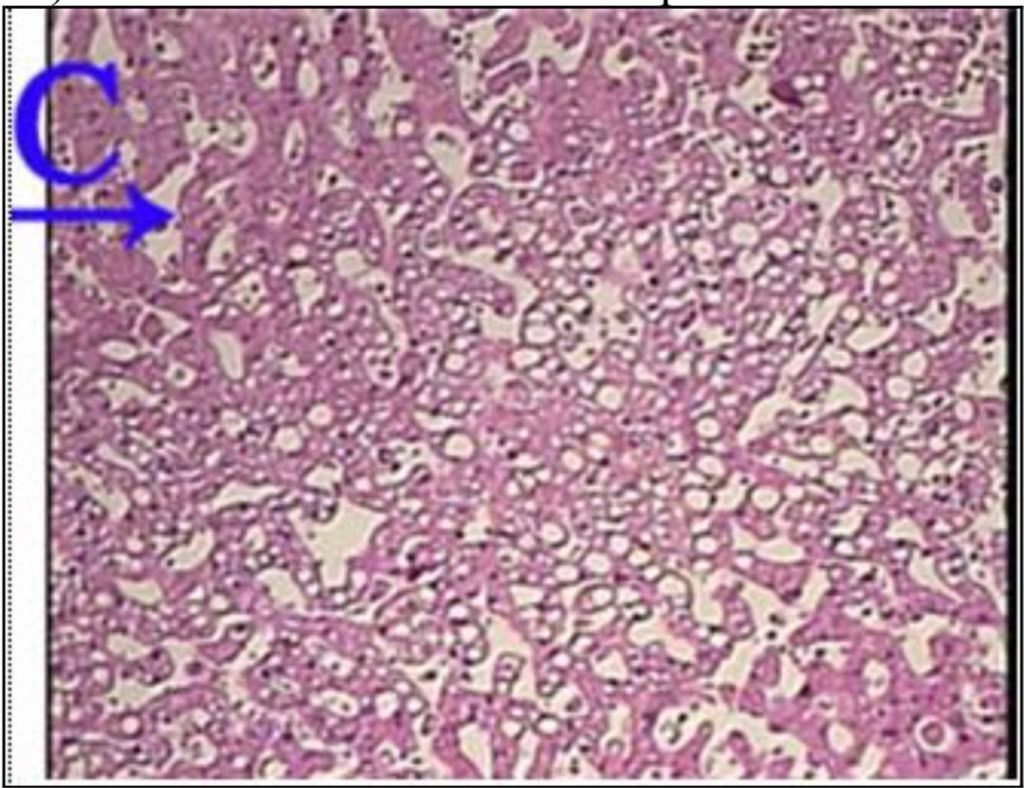

Question 87

Question

What is the correct answer at point A?

Answer

• - veine centrolobulaire

• - stéatose médiolobulaire

• - travée hépatocellulaire

• - vacuole de graisse

• - noyau de l’hépatocyte

Question 88

What is the correct answer at point B?

Question 89

What is the correct answer at point C?

Question 90

What is the correct answer at point D?

Question 91

What is the correct answer at point E?